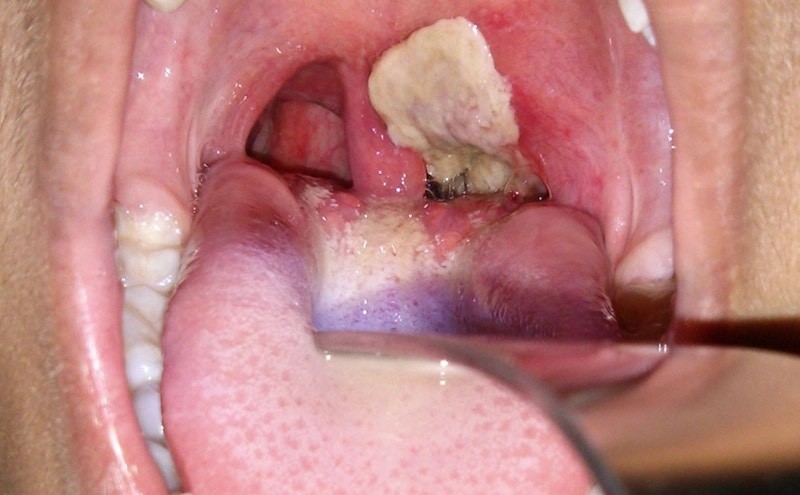

Biểu hiện bệnh có thể từ nhẹ đến nặng, thường có giả mạc màu trắng ở tuyến hạnh nhân, hầu họng, thanh quản, mũi, có thể xuất hiện ở da, các màng niêm mạc khác như kết mạc mắt hoặc bộ phận sinh dục, trường hợp nặng có thể gây biến chứng và tử vong.

Người mắc bệnh bạch hầu thường xuất hiện những triệu chứng điển hình như sốt nhẹ, họng đỏ, nuốt đau, ho, khàn tiếng, mệt, da hơi xanh, chán ăn. Sau 2-3 ngày, người bệnh xuất hiện giả mạc mặt sau hoặc hai bên thành họng, có màu trắng ngà, xám hoặc đen. Giả mạc dai, dính, dễ chảy máu. Đây là dấu hiệu quan trọng nhất để phát hiện bệnh.